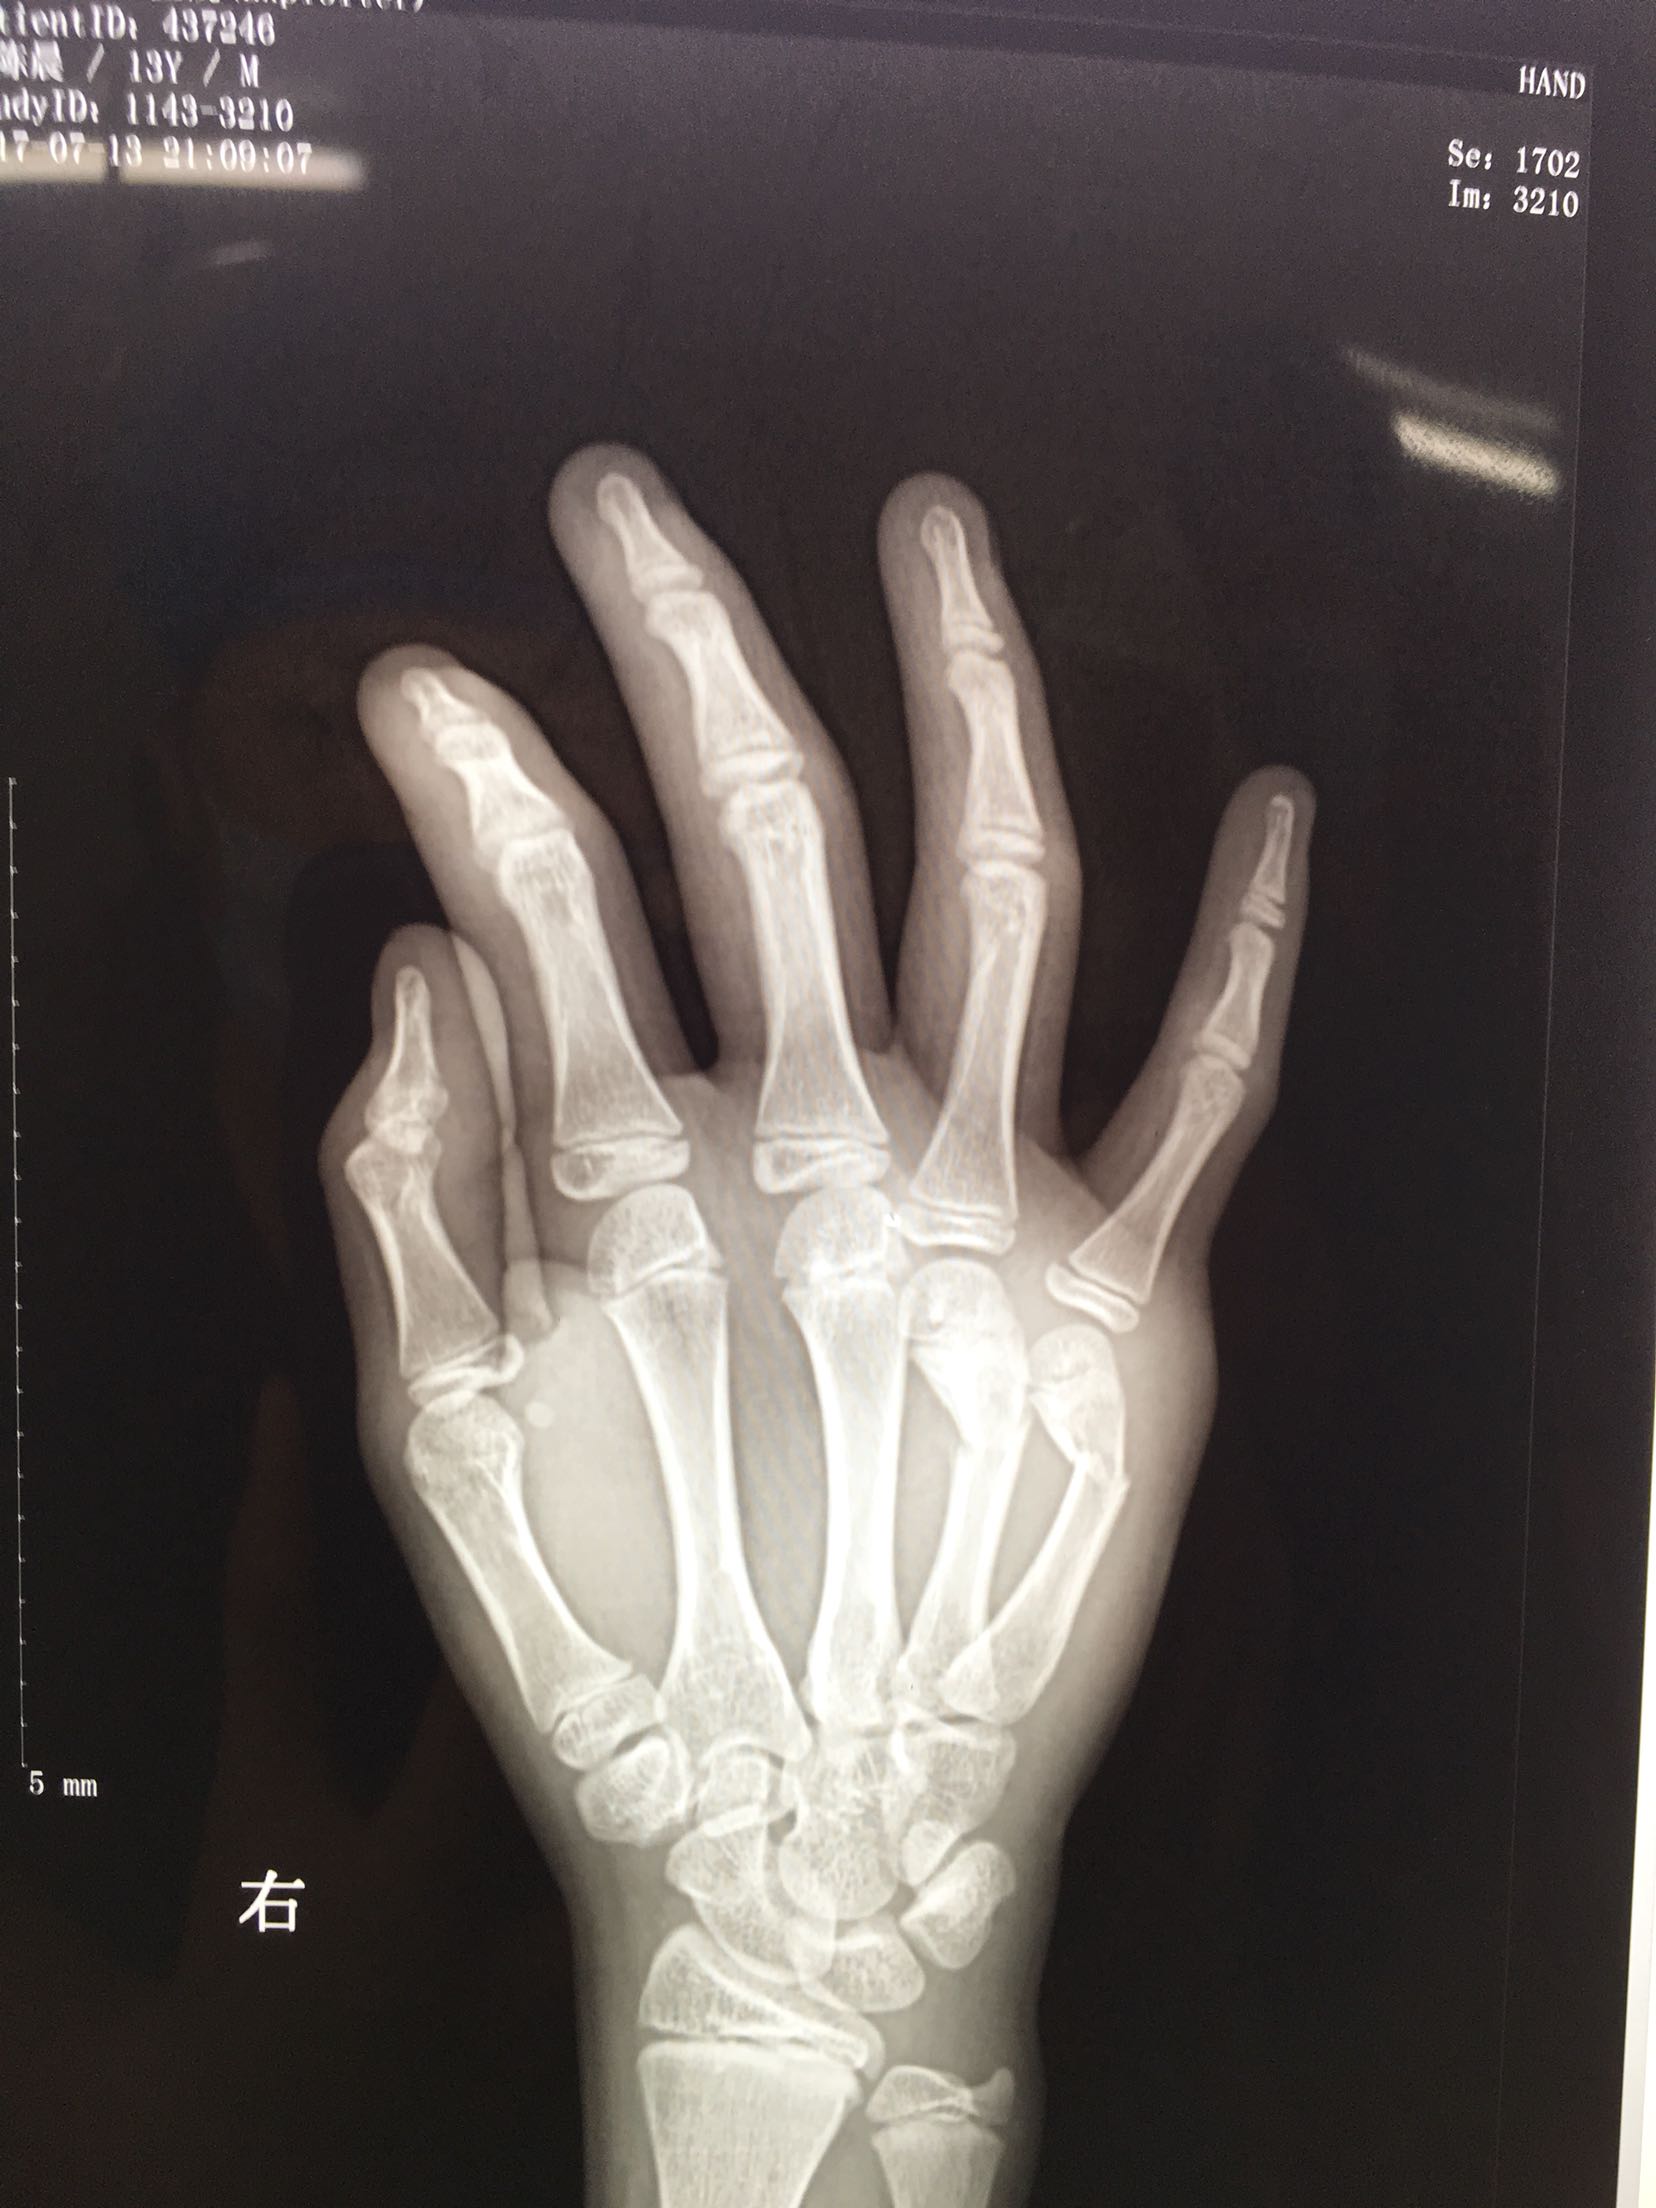

右第四,五掌骨骨折(微创)

患者,男,13岁,撞伤后右手肿痛,活动受限1天入院。

右手肿胀明显,局部皮色青紫,皮温稍高,第四,五掌骨头处压痛,纵叩痛阳性,掌指关节活动受限,末梢血运感觉正常。